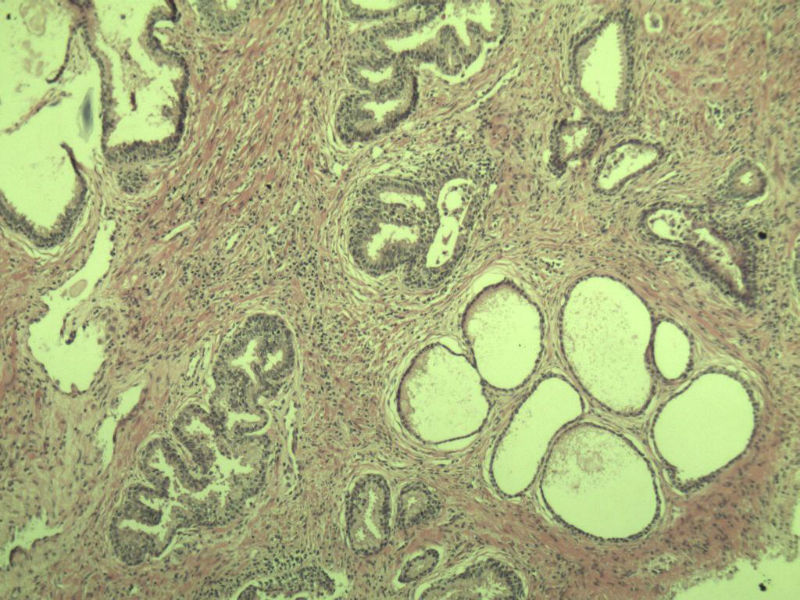

男 75岁 因排尿困难半年行前列腺切除术,体积 4 × 3 × 2.5 cm3,切面灰白,实性,质韧。请各位老师看看 有问题没? 谢谢了!

良性前列腺增生伴尿路上皮化生

前列腺增生症伴鳞化

前列腺增生,有腺瘤样结节形成。

前列腺增生伴尿路上皮鳞化及Brown巢形成,未见恶性。

前列腺结节性增生